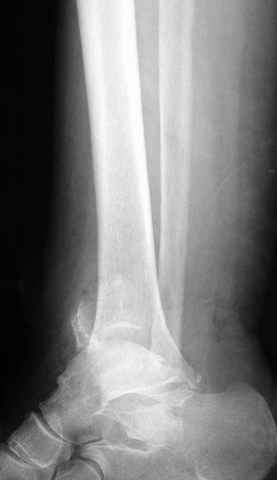

Re: ANKLE FRACTURE

Alexander Chelnokov 12 Сентябрь 2004, 15:11

Я вот все в толк не возьму смысл отдельной фиксации малоберцовой кости пластинкой, если все равно будет аппарат с фиксацией стопы, т.е. возможностью провести спицы в пятку, таран, наружную лодыжку и еще черт-те куда. Остеосинтез пластинкой выглядит логичным в случае, когда наружная фиксация планируется как временная. Но тут-то аппарат будет окончательным фиксатором.

Еще, кстати, о фиксации лодыжки, если уж непременно хочется ее отдельно стабилизировать - при таком характере перелома замечательно должен сработать предложенный проф. Лазаревым с соратниками способ фиксации напряженной V-образной спицей. Опять же, открытая репозиция не нужна, мы делаем непрямую репозицию именно аппаратом. В приложении пример, там перелом малоберцовой куда менее поперечный, чем в данном случае, но все равно получилось закрыто без пластинки.

I can't realize why plate fibula separately if anyway external fixator including the foot is planned, i.e. one may insert wires to the talus, calcaneus, lateral malleolus and anywhere else. Plating looks reasonable if only temporary ex-fix is planned, but in the case it will be definitive.

A propos fibular fixation if one is eager to stabilize it separately. In the fracture pattern a way of closed fixation by V-shaped stressed wire (advanced by colleagues from Moscow, prof. Lazarev A.F. et al.) must be excellent. We use indirect closed reduction by the external fixator. Example attached, that fibular fracture is even more suitable for plating but the wire did the job.